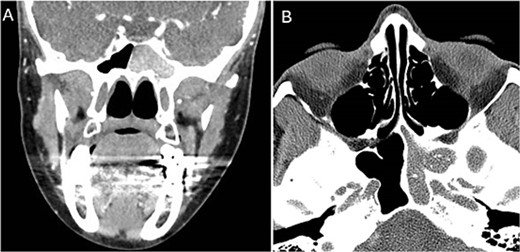

A 36 years-old man with no previous history of medical disease presented to the otolaryngology clinic with a chief complaint of headache that was associated with pressure feeling mainly in the occipital area. He also reported a post-nasal drip. The patient underwent a non-contrast paranasal sinus CT scan (Fig. 1) that demonstrated an isolated sphenoid sinus homogenous opacification, most likely representing sphenoid fungal ball. A decision was made to proceed with endoscopic sphenoidotomy (Fig. 2) to clean and remove the debris, which confirmed the diagnosis of sphenoid sinus fungal ball.

Coronal (A) and axial (B) images of a nonenhanced CT scan of the paranasal sinuses showing left sphenoid sinus complete homogenous opacification.